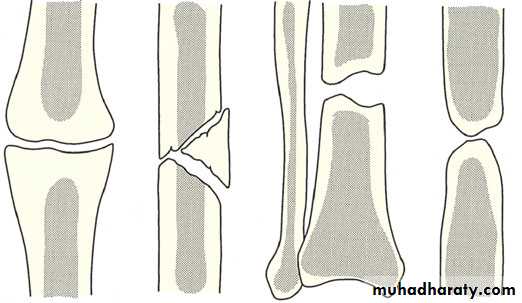

problems of union:

Sometimes bone healing is delayed and takes more than usual time here we call it DELAYED UNION.

Sometimes the fracture fail to unite and the problem is called NON-UNION, this can be atrophic non-union where bone completely fail to form around the fracture,

or its called hypertrophic non-union where there is excessive large callus that cannot pass

through the fr line and bridge the fr fragments.

Radiologically atrophic nonunion shows;

Maintenance of the fr line.

Resorbtion of the ft end that will show a rounded appearance rather than the sharp fr ends.

Local sclerosis of the fr ends.

Sometimes abnormal position or displacement of the fragments.

Hypertrophic non-union gives the radiological appearance of maintenance of the fr line with extensive callus proximal and distal to it, also abnormal position of the fragments may be seen. The appearance sometimes refereed to as elephant foot or hours hoof appearance.

Sometimes bone unites in an abnormal position, this is called MAL-UNION, this can lead to various deformities and functional impairments.